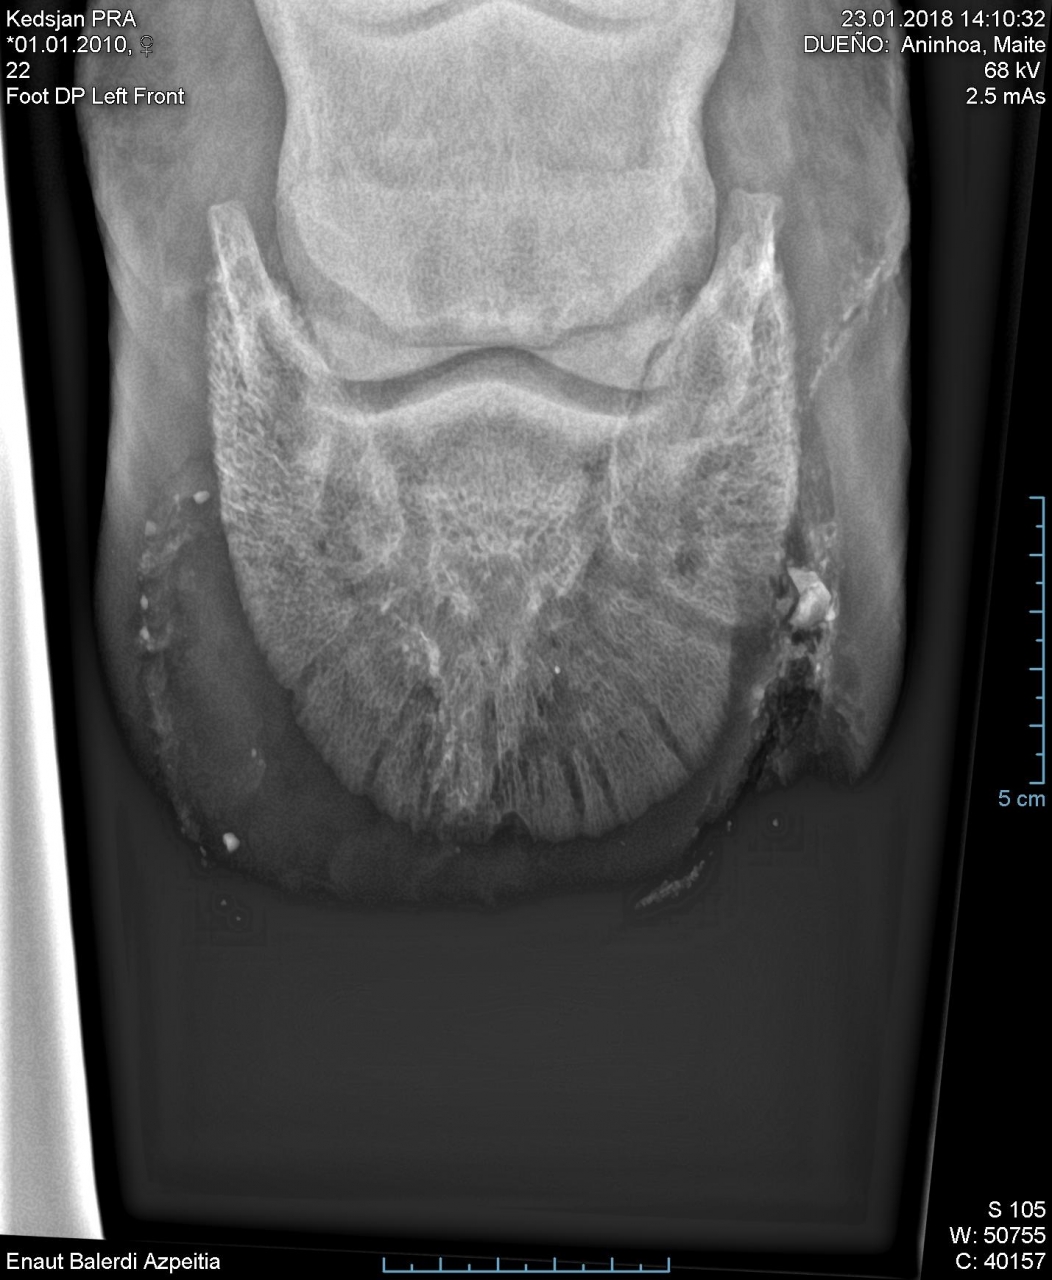

Par Cocktail_jet : le 05/12/19 à 12:02:16

| Dire merci | voici une photo de 2016![]() plus jamais je réouvre le pied de mon cheval comme ca je préfère mettre 3 semaines d'antibios |